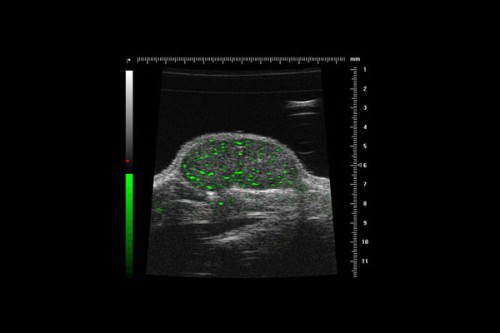

New Delhi, Dec 12 (IANS) The ultrasound contrast agents (microbubbles) market is driven by their role in enhancing diagnostic capabilities and revolutionising treatment methods, according to a report on Tuesday.

The report from GlobalData, a data and analytics company, showed that the demand for microbubbles will stem from the growing preference for non-invasive procedures, personalised medicine, and innovations in imaging technology -- especially in cardiology, oncology, and neurology, where precise imaging is critical for accurate diagnosis and treatment monitoring.

“Ultrasound imaging is experiencing rapid growth due to its non-ionizing nature, portability, and cost-effectiveness. Its real-time imaging capabilities are useful for preventive screening and monitor changes over time, and with minimal risks and increased accessibility it is the preferred choice for various medical applications,” said Ashley Clarke, Medical Analyst at GlobalData, in a statement.